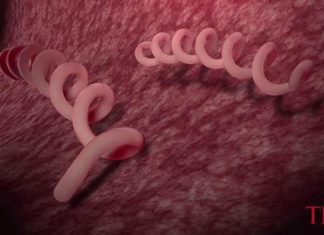

Syphilis cases in California drive a record-setting year for STIs nationwide...

In certain circles of San Francisco, a case of syphilis can be as common and casual as the flu, to the point where Billy...